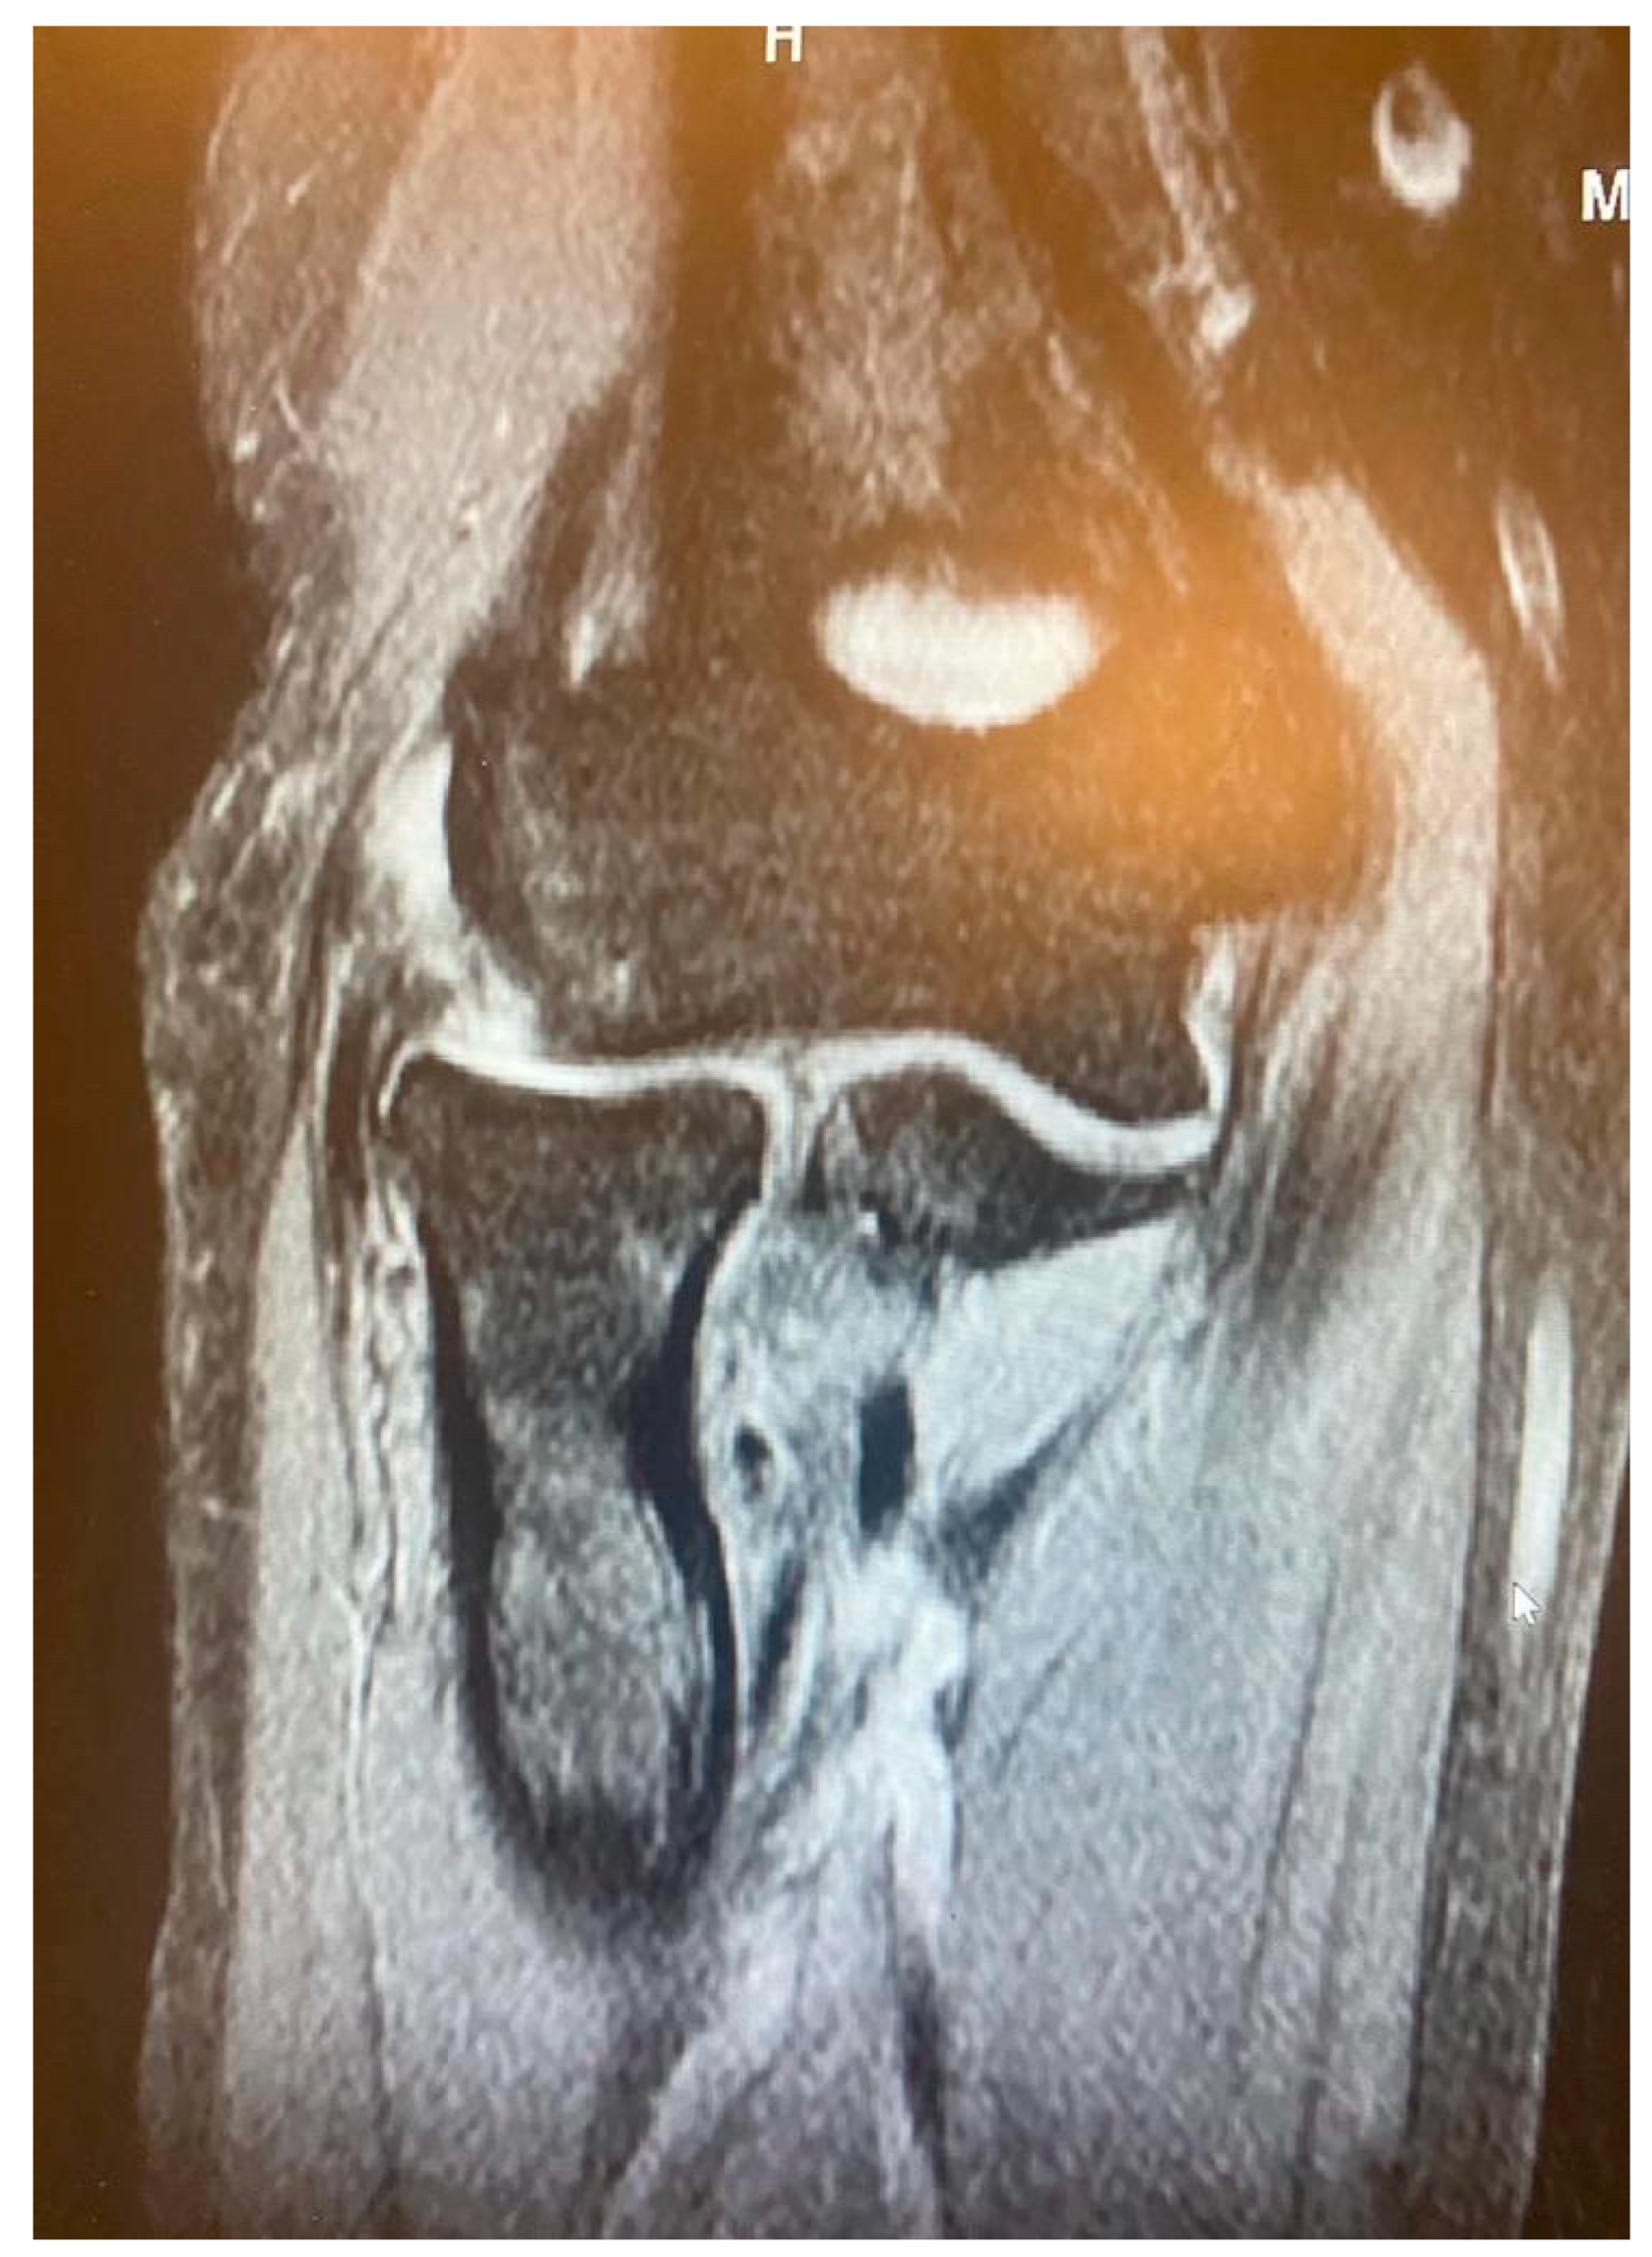

Figure 5.

Complete CEO rupture without retraction [courtesy of C.K.].